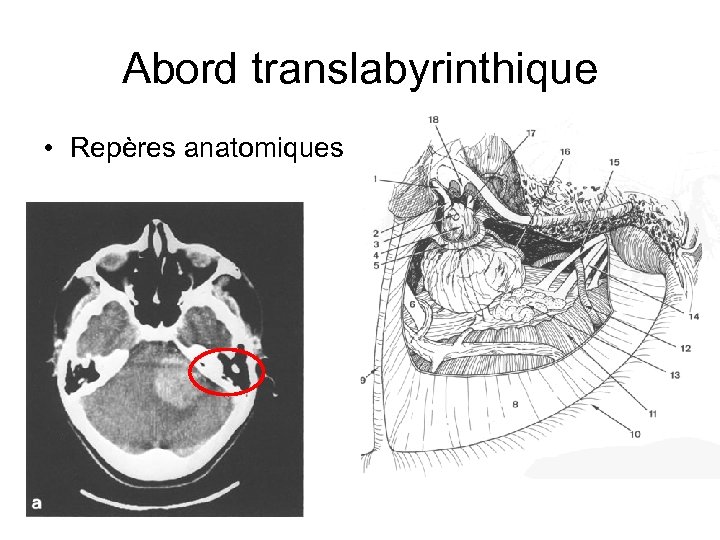

Abord translabyrinthique • Repères anatomiques

Abord translabyrinthique • Repères anatomiques